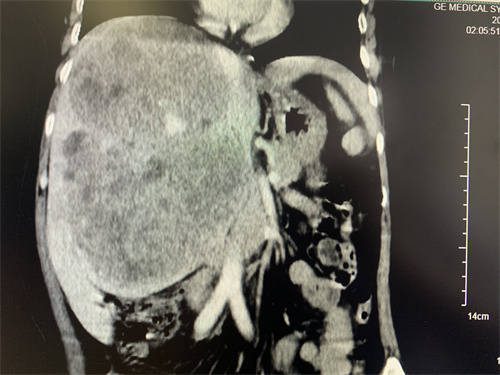

1月14日下午,外科楼6楼的等候区,刘某的儿子在手术室外面忐忑不安地来回踱步。手术室里面,罗宏武教授和张玉平副教授带领的手术团队却在有条不紊地探“腹”取“瘤”,术中探查瘤体包膜完整,成膨胀性生长。由于瘤体长时间地挤压,肝动脉、门静脉及胆管完全失去了正常的解剖结构,且巨大的瘤体严重限制术者的视野和操作空间,但团队凭借精湛的手术技能和丰富的手术经验,经过5个钟头的鏖战,沿着中肝静脉、下腔静脉和瘤体边缘仅5mm的缝隙最终成功地将瘤体侵犯的右半肝及尾状叶完整切除,最大程度地保留了残肝功能和肝中静脉完整,取出的标本体积为:24x18x16cm,重量为2.35kg,为两个巨大瘤体的融合灶。术后,在肝胆胰外科Ⅰ科护理团队的悉心护理下,患者身体状况恢复良好,各项检验指标正常,目前已能下床活动,而刘某儿子的脸上也绽放出了久违的笑容。

据罗宏武主任介绍,很多肝脏恶性肿瘤一经发现往往已是中晚期,多不具备手术条件。该例患者肿瘤达24cm,临床很少见,但无卫星转移结节,无血管癌栓,手术有望获得良好效果。近年肝癌治疗有很大进展,新兴的转化治疗给既往认为不具备手术条件的肝癌患者争取了手术机会,降低了复发风险。迄今为止,肝胆胰外科Ⅰ科已为多例巨大肝癌患者成功实行解剖性病变肝叶(段)切除术,也通过短期的转化治疗使多例无手术条件的患者重获手术机会,包括腹腔镜下巨大肝癌和严重肝硬化患者的肝癌切除术,积累了丰富的手术经验,大幅度地延长了患者的生存期,改善了患者的生存质量,提高了医院的影响力。